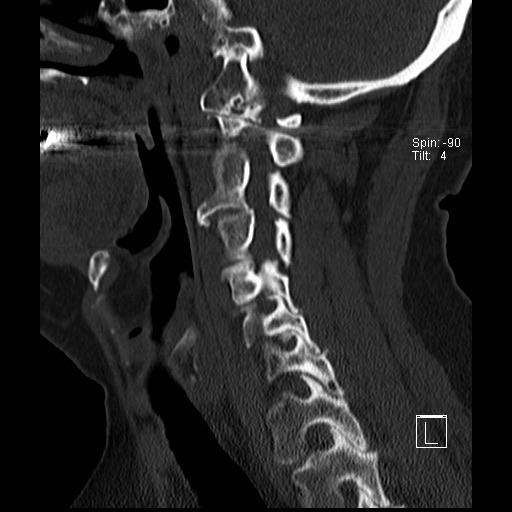

Lồng nền sọ

Lồng nền sọ, còn gọi là sụt lún sọ não hay ấn nền sọ, xảy ra ở 5-10% bệnh nhân viêm khớp dạng thấp cột sống cổ.

Trong lồng nền sọ, mỏm răng sa vào lỗ chẩm làm thu hẹp không gian dành cho tủy sống.

Biểu hiện lâm sàng đa dạng, từ đau đầu mạn tính, hạn chế vận động cổ đến suy giảm thần kinh cấp tính (chèn ép tủy sống và thân não, có thể dẫn đến liệt hoặc thậm chí tử vong nếu cổ bị di chuyển ở một số tư thế nhất định).

Hình ảnh

Cuộn xem các lát cắt CT.

Có hình ảnh di chuyển lên trên của mỏm răng vào lỗ chẩm.